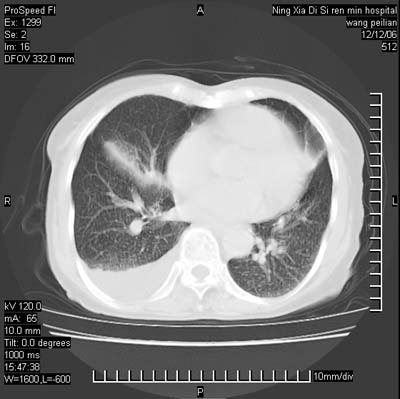

标题: CT5609:胸部:女77 病史不详

两肺可见多个大小不等的结节,左侧有胸水,纵隔淋巴结增大,考虑是细支气管肺泡癌

两肺尖纤维索状影,两下肺结节块状影,且有钙化灶,右胸腔积液。考虑肺结核并胸膜炎。

两肺尖纤维索状影,两下肺结节块状影,且有钙化灶,右胸腔积液。考虑肺结核并胸膜炎肺间质纤维化

考虑:1、慢性支气管炎合并全小叶型肺气肿、间质纤维化;

2、双肺结核;

3、右侧胸膜炎(积液)。

1、双肺继发型肺结核(以纤维、增殖灶为主);

2、右侧胸腔积液;

3、其余符合老年肺改变。

双肺见多个结节状及条索状影,双侧胸腔积液,右侧叶间积液,考虑结核性胸膜炎